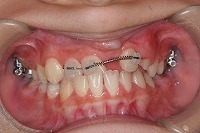

反対咬合と前歯が生えてこない事を主訴に来院された、10歳4か月の男の子です。診断「下顎骨の過成長による骨格性反対咬合で上顎正中の左方偏位と埋伏歯を伴う」1期治療で反対咬合の解消と埋まっていた前歯を牽引しました。